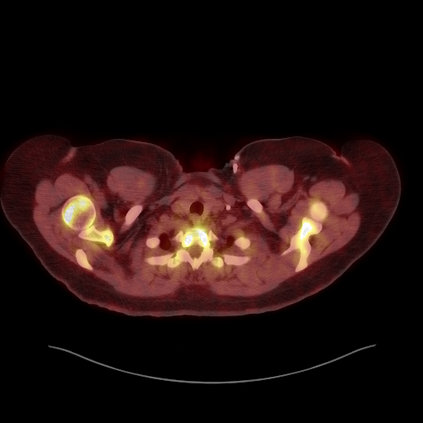

Medical images play a crucial role in assisting diagnosis, remote consultation, and academic research. However, during the transmission and sharing process, they face serious risks of copyright ownership and content tampering. Therefore, protecting medical images is of great importance. As an effective means of image copyright protection, zero-watermarking technology focuses on constructing watermarks without modifying the original carrier by extracting its stable features, which provides an ideal approach for protecting medical images. This paper aims to propose a fragile zero-watermarking model based on dual quaternion matrix decomposition, which utilizes the operational relationship between the standard part and the dual part of dual quaternions to correlate the original carrier image with the watermark image, and generates zero-watermarking information based on the characteristics of dual quaternion matrix decomposition, ultimately achieving copyright protection and content tampering detection for medical images.